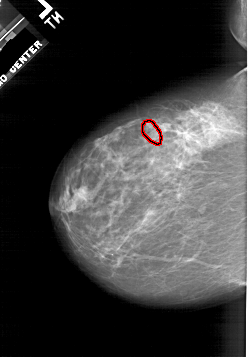

A_1941_1.RIGHT_CC

RIGHT_CC LINES 5326 PIXELS_PER_LINE 3751 BITS_PER_PIXEL 12 RESOLUTION 43.5 NON_OVERLAY